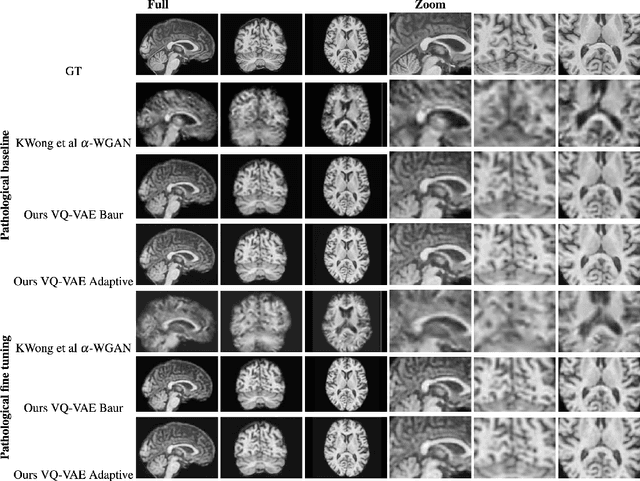

Abstract:The increasing efficiency and compactness of deep learning architectures, together with hardware improvements, have enabled the complex and high-dimensional modelling of medical volumetric data at higher resolutions. Recently, Vector-Quantised Variational Autoencoders (VQ-VAE) have been proposed as an efficient generative unsupervised learning approach that can encode images to a small percentage of their initial size, while preserving their decoded fidelity. Here, we show a VQ-VAE inspired network can efficiently encode a full-resolution 3D brain volume, compressing the data to $0.825\%$ of the original size while maintaining image fidelity, and significantly outperforming the previous state-of-the-art. We then demonstrate that VQ-VAE decoded images preserve the morphological characteristics of the original data through voxel-based morphology and segmentation experiments. Lastly, we show that such models can be pre-trained and then fine-tuned on different datasets without the introduction of bias.